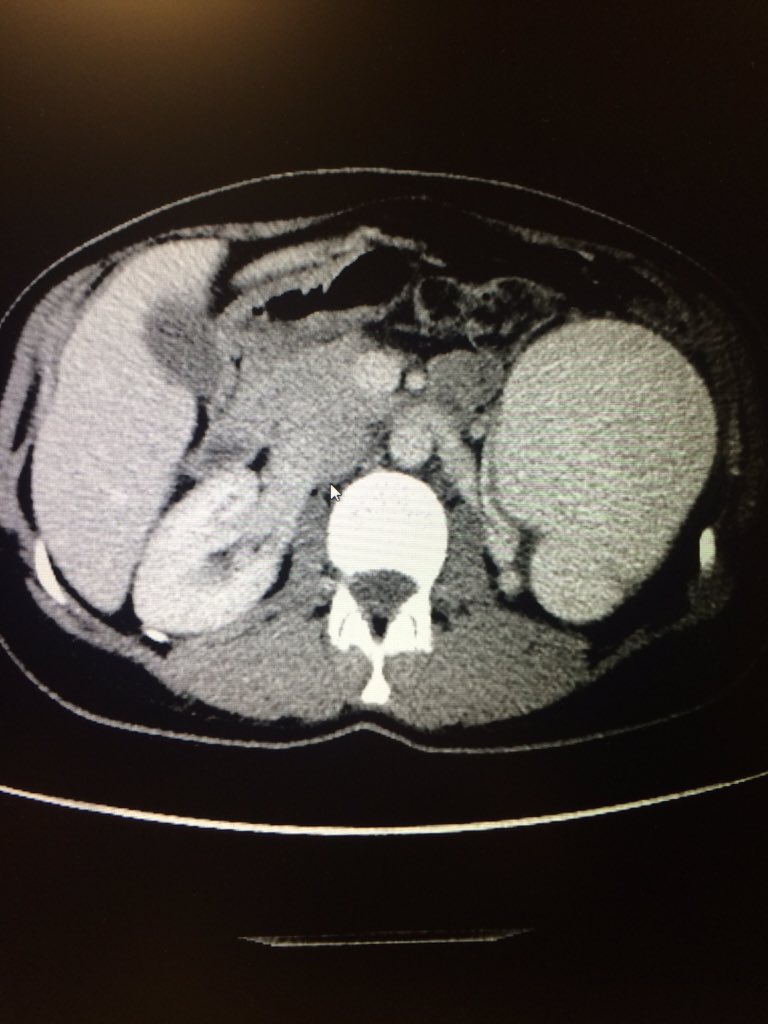

72 yo w/acute urinary retention 2/2 BPH. Remote h/o TURP. VIR consulted for PAE. Great clinical result. For more case info check out AlbanyIR.com/pae-case-1 and AlbanyIR.com/prostate-arter… for more about PAE. #IRad #PAE @SIRRFS @JVIRmedia